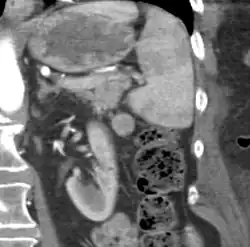

Gross pathology of an accessory spleen -

If splenectomy is performed for conditions in which blood cells are sequestered in the spleen, failure to remove accessory spleens may result in the failure of the condition to resolve.[1] During medical imaging, accessory spleens may be confused for enlarged lymph nodes or neoplastic growth in the tail of the pancreas,[5] gastrointestinal tract, adrenal glands or gonads.[2]